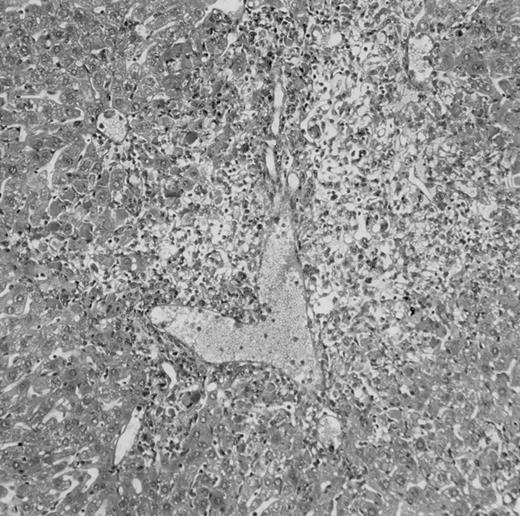

Histologic findings. Organs were collected at different times after BMT and tissue sections were stained with hematoxylin and eosin. Original magnifications for spleen (left) and liver (right) are ×40 and ×100, respectively. (A) B6 mice receiving FVB BM plus EpTK T cells. (B) Control group receiving BM only.

(C) B6 mice receiving FVB BM plus EpΔTK T cells and treated with GCV. (D) B6 mice receiving FVB BM plus EpΔTK T cells, treated with GCV, and developing a late onset GVHD (day 54).

FVB BM-grafted B6 mice: a model of lethal GVHD.We developed a model of GVHD resulting in 100% mortality soon after BMT using FVB mice, a strain not previously used as BM donors in experimental allogeneic BMT. We tested different combinations of recipient irradiation doses, as well as injected BM cell and CD3+ peripheral T-cell numbers. When 10-Gy–irradiated B6 mice were reconstituted with 107 FVB BM cells, we observed prolonged survival, whereas all ungrafted animals died before day 16 (Fig 2). In these conditions, more than 98% of splenocytes were of donor origin (Fig 3A). When 107 CD3+ peripheral T cells from mice of FVB genetic background were added to the FVB BMT, all animals died of GVHD between days 7 and 34 (Fig 2). Similar results were obtained using either PBS-treated mice receiving EpTK or EpΔTK peripheral T cells or GCV-treated mice receiving FVB nontransgenic peripheral T cells. Notably, this observation also indicates that both TK- and ΔTK-expressing T cells in the absence of GCV are fully competent to induce a lethal GVHD. Histopathologic examination of spleen and liver of these animals showed characteristic GVHD lesions such as (1) architecture disruption, necrosis, and congestion in the spleen; (2) hepatic periportal necrosis; (3) mononuclear portal infiltrates; and (4) endothelialitis of portal or centrolobular veinules (Fig 4A). By comparison, B6 mice receiving only FVB BM had a normal histology (Fig 4B).

Using this delivery mode, we observed that mice receiving a 7-day GCV treatment initiated at the time of transplantation were protected from GVHD. At day 60, the survival rate was 100% in the GCV-treated group receiving EpTK CD3+ T cells, and was still 92% at the end of a 120 day follow-up (Fig 2A). Protected mice were apparently healthy, presented no visible skin lesions, and gained weight comparably to controls receiving only BM (data not shown). Hematologic reconstitution was analyzed by flow cytometry at different times from day 14 to day 212. Splenocytes of GCV-treated animals were of donor H-2q origin in the B-cell (B220+) and non–B-cell (B220−) compartments, the latter containing donor Thy1.1+ T cells but no recipient Thy1.2+ T cells (Fig 3B). Finally, histological analysis in these animals showed nodular architecture in the spleen and no significant hepatocyte necrosis or portal mononuclear cell infiltrates in the liver (not shown) and similar to control animals receiving only BM. Taken together, these data indicate that a GCV treatment, administered at the onset of allogeneic BMT and with a course as short as 7 days, abrogates GVHD and allows a full recovery from the lethal irradiation.

Protection from GVHD was slightly less efficient in the group receiving EpΔTK CD3+ T cells. The survival rate was 79% at day 60 and 67% at day 120 (Fig 2B). However, two different outcomes must be distinguished. On the one hand, a majority of mice behaved as GCV-treated animals receiving EpTK T cells. They were apparently healthy, presented no skin lesions during a 120-day observation period, and showed complete donor-type hematologic reconstitution. There were no histological signs of GVHD in the spleen or liver (Fig 4C).

On the other hand, 5 of 19 mice exhibited signs suggesting the occurrence of a delayed GVHD (Table 1). Clinically, these animals presented weight loss and/or skin lesions on ears, neck, limbs, or abdomen, but only after day 40. In the absence of any further GCV treatment, 2 mice died 14 and 29 days after the occurrence of these signs (Table 1A) with histological signs of severe GVHD (Fig 4D). These results suggest that, in these mice, the 7-day GCV treatment was sufficient to prevent early, but not delayed GVHD.